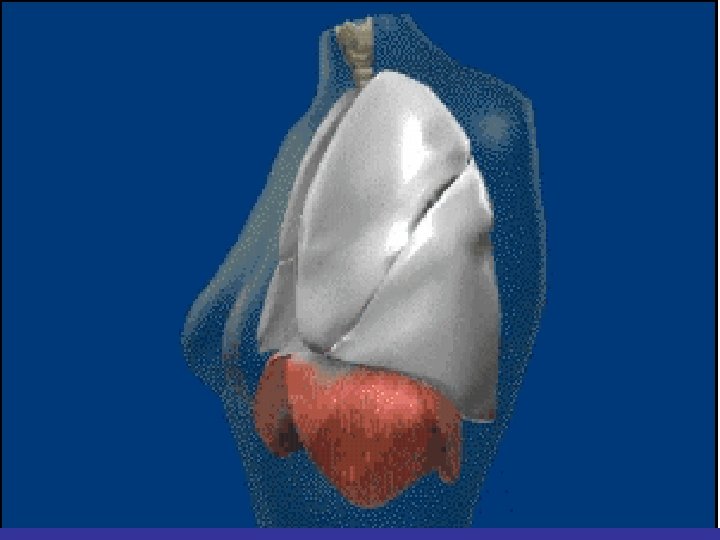

Lobes and Fissures

lateral view ? ! can detect otherwise hidden masses